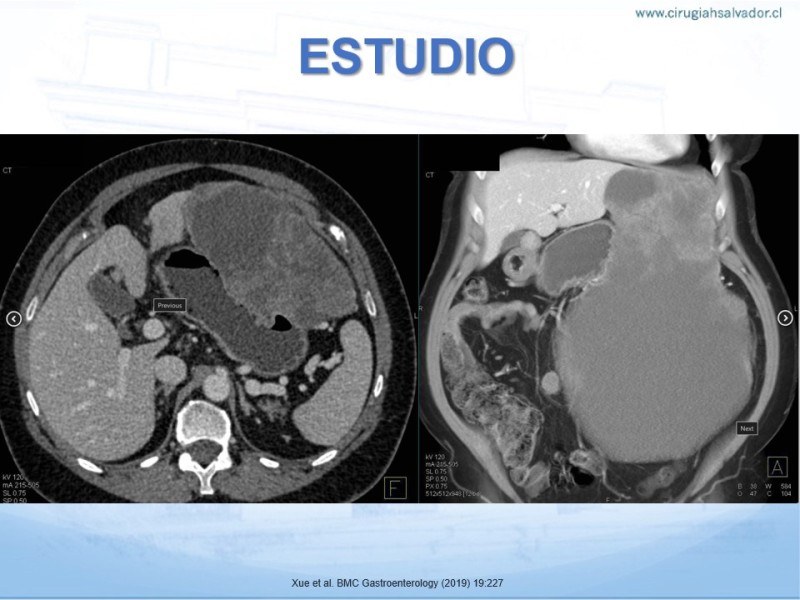

Gastrointestinal Stomal Tumor (GIST) Gástrico

Digestivo Alto